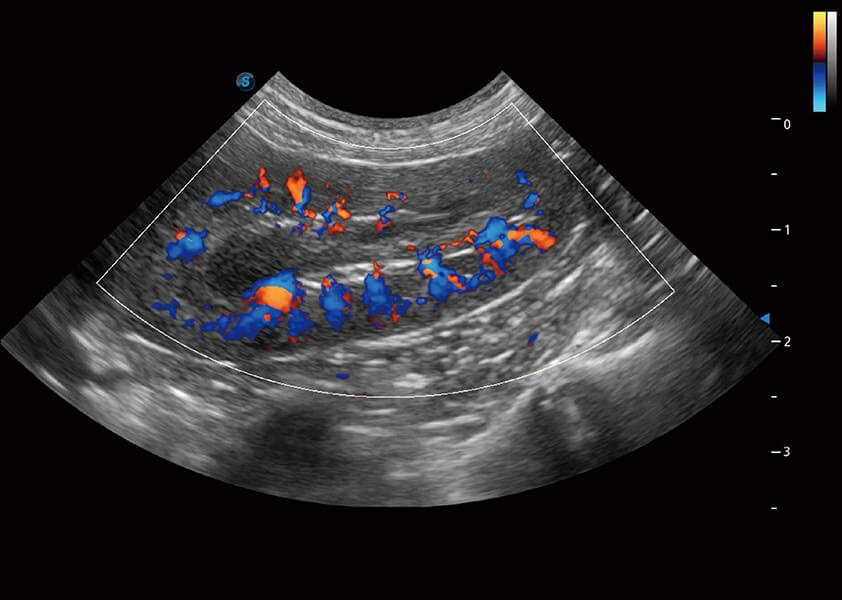

ProPet 60 作为一款高端台式动物超声设备,为动物医生的日常诊断提供了一系列贴合动物临床需求、解决临床实际问题的高级成像功能。凭借全系列高清探头,满足医生对腹部、心脏、生殖、浅表、肌骨等成像的所有需求,切实帮助您提升检查效率,提高诊断信心。

动物是人类最亲密的朋友和最值得信赖的伙伴。开立医疗也一直致力于探索动物专用的超声影像解决方案。 全新推出的ProPet系列,是开立在动物超声影像智能化、专业化、精准化的一次跨越式革新。动物不能用言语来表述自己的不适,通过超声影像,ProPet系列搭建了动物医生与不同物种沟通的“桥梁”,为动物医生注入了“治愈之力”。